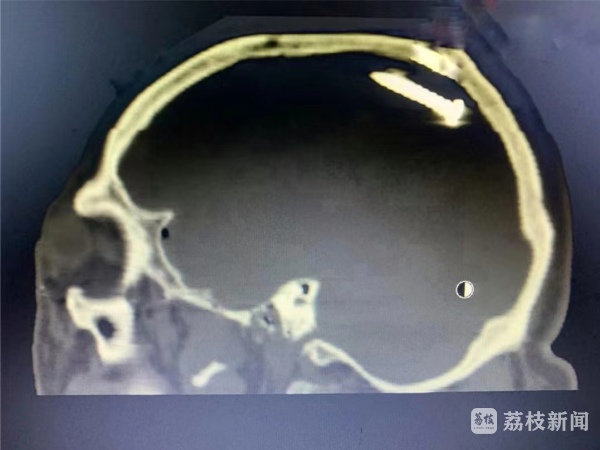

7月10日中午,正在家中休息的张勇接到医院电话,120急救车送来一位52岁的脑外伤患者,脑内有钉样异物,一侧瞳孔已经散大。身旁的工友描述,施工时使用射钉枪,不小心水泥钉从额部飞进脑门。结合影像检查及术中所见,可以判断水泥钉是从左前额进入颅内,穿过左脑,撞击后方颅骨后又转向前上方。途中转了个圈,形成长约二十几厘米的脑内伤道,割破大脑镰,还搅破了很多小血管,形成小的创伤性动脉瘤,并形成了大量伤道内血肿。

“所幸术前备了c臂、瘤夹等,几经周折,花费了10余小时终于顺利清除钢钉、碎骨片及大量血肿,复查CT提示手术效果满意。”张勇主任说,只要患者顺利渡过感染关,预后应该是比较理想的